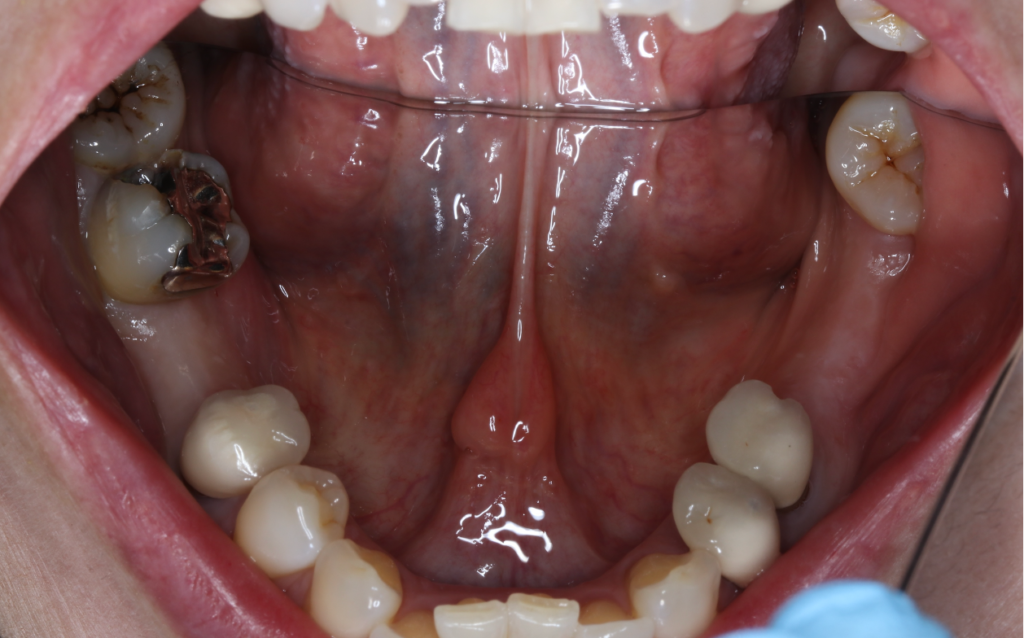

インプラント症例④

年齢 50代女性

治療期間 4ヶ月

インプラントメーカ ジンマーインプラント

治療内容 カスタムアバットメント、上部ジルコニア

治療箇所 左下6番

治療費用 380,000円